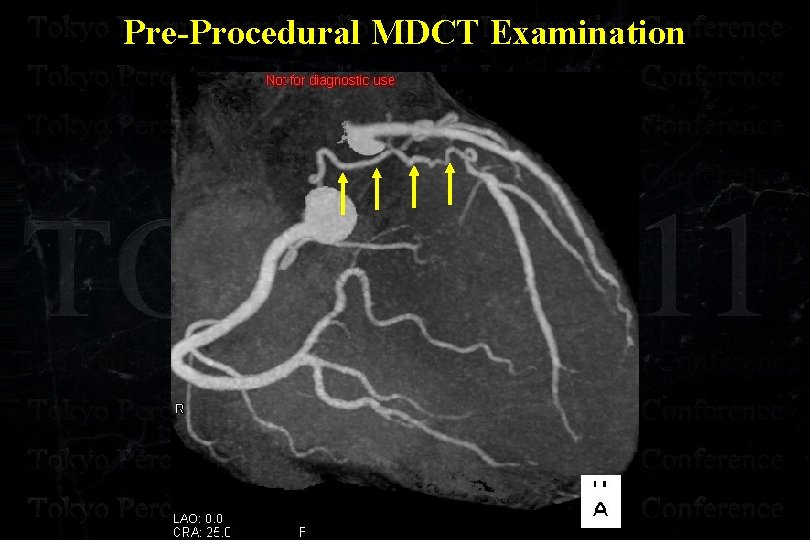

Pre-Procedural MDCT Examination